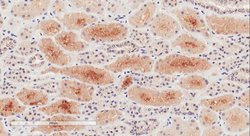

Invitrogen™ NPR3 Polyclonal Antibody

Additional Information: The immunizing peptide represents the cytoplasmic part of the protein. This antibody is tested in Peptide ELISA: antibody detection limit dilution 1:16,000.

| Immunohistochemistry (Paraffin), Western Blot | |